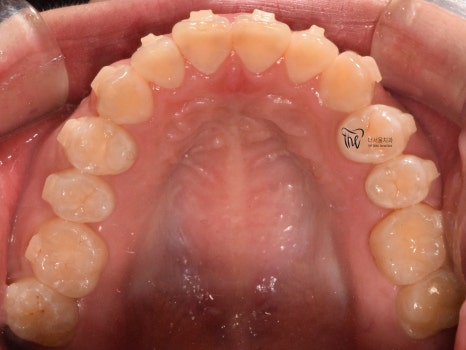

구강 내 사진을 보면, 전형적인 Open bite 의

형태를 띄고 있는 것을 보실 수 있습니다.

그 정도는, 그렇게 심하지는 않으나

치아교정 을 받지 않는다면 턱관절 에

더 큰 문제를 일으킨다는 것을 본인 스스로도

잘 알고 있었기 때문에 저에게 진료를

의뢰했었습니다.